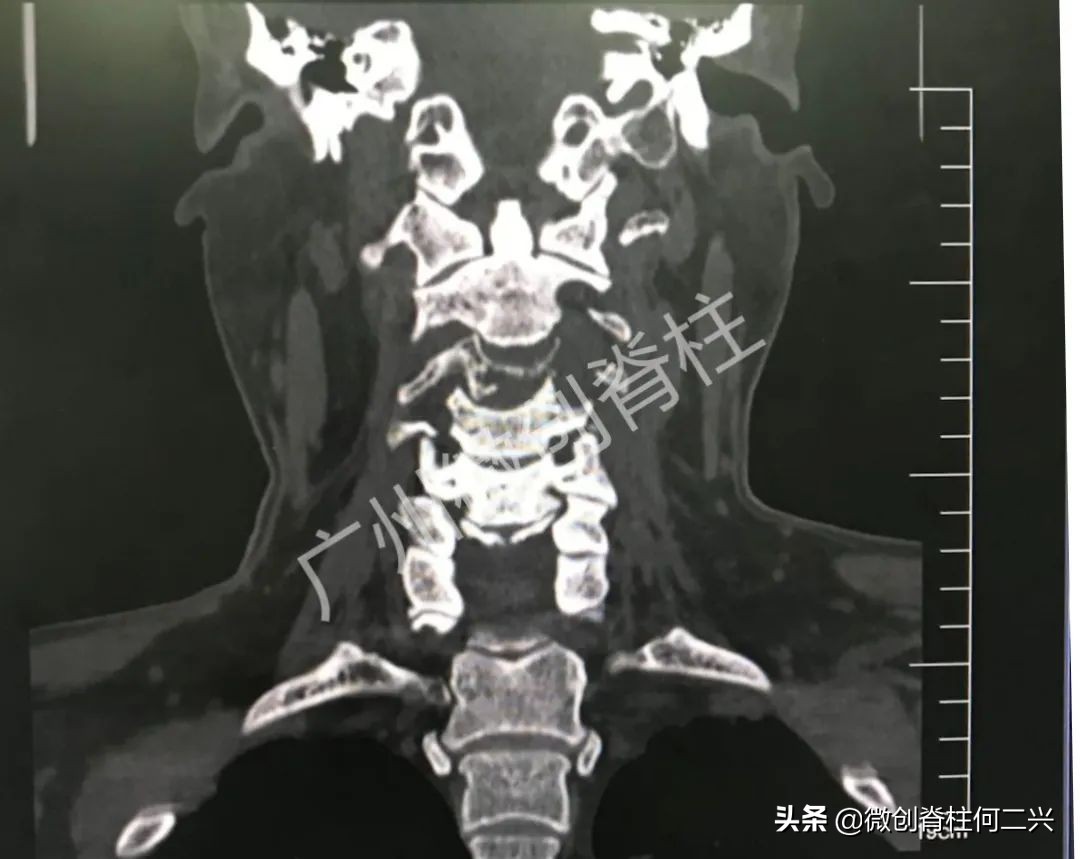

患者既往有肝癌病史,在外院检查结果为:颈3椎体转移。了解情况之后,何二兴主任结合患者在当地医院所拍MR,并完善了颈椎CT、颈椎正侧位等检查之后,给出了明确的诊断:肝癌颈3椎体转移、颈3椎体压缩性骨折、肝癌。

何二兴主任介绍,该患者肝癌一年多,并不是转移在颈6椎体,而是转移至第三颈椎,肿瘤组织侵犯整个椎体,导致后者塌陷,颈椎失去稳定性,向后膨出的瘤体将脊髓压迫,随时都可能发生四肢瘫痪甚至死亡。